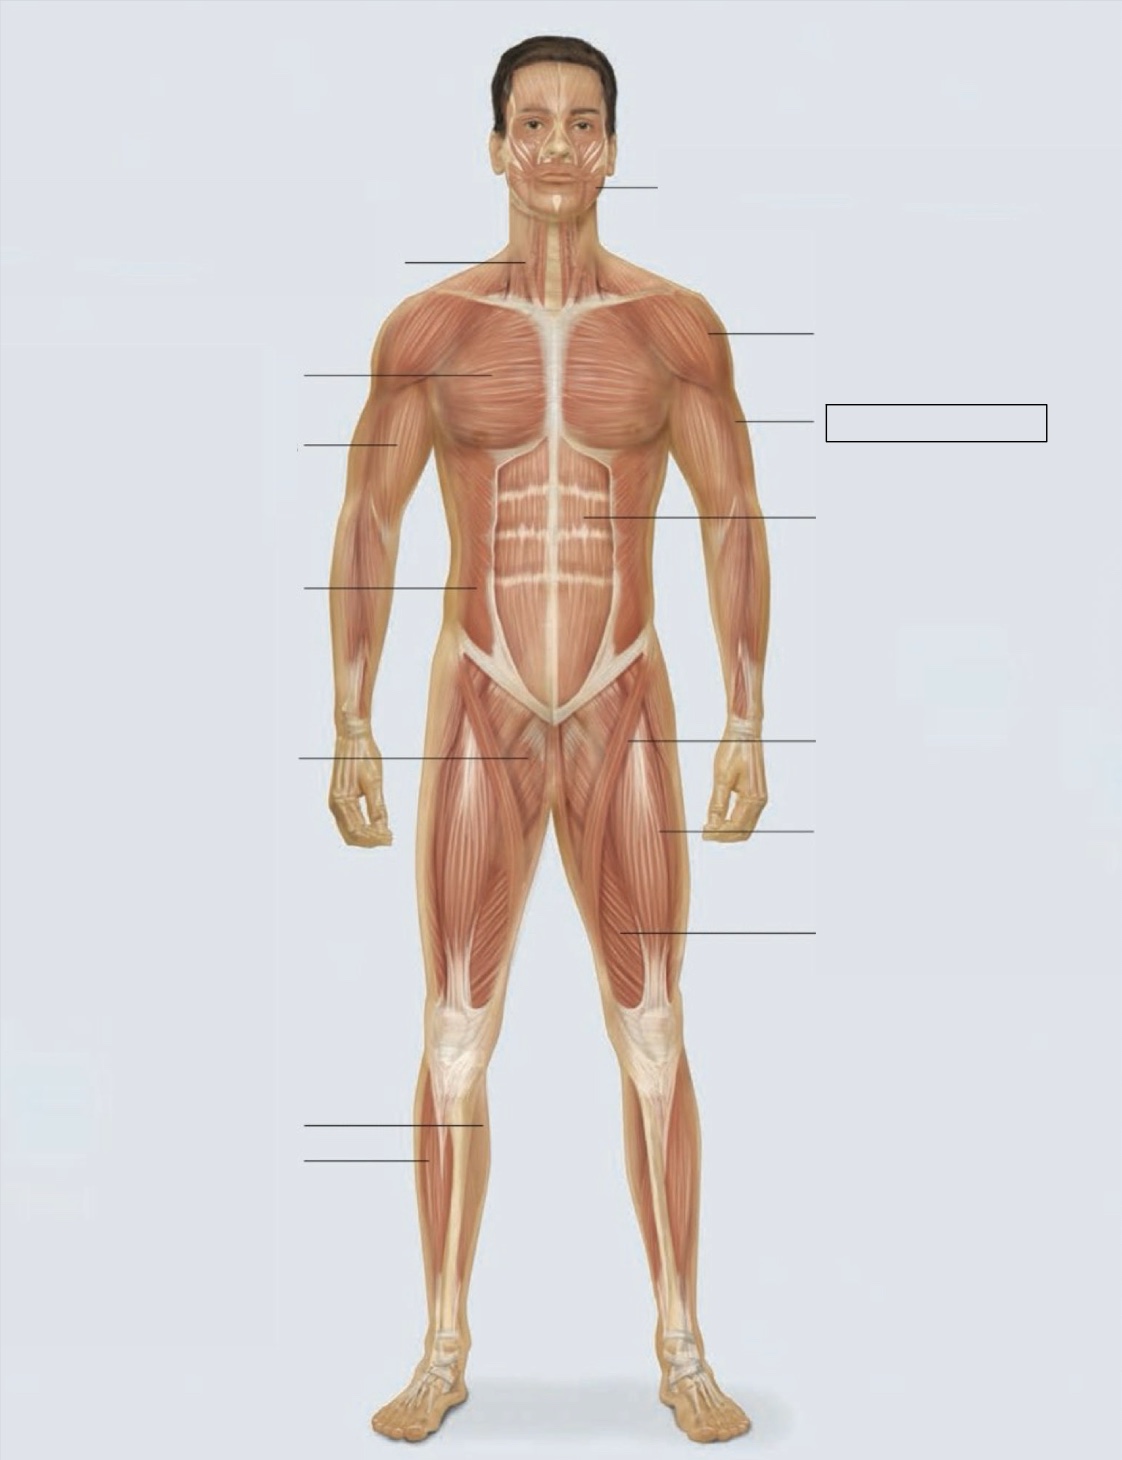

masseter

deltoid

triceps

rectus abdominis

sartorius

quadriceps femoris